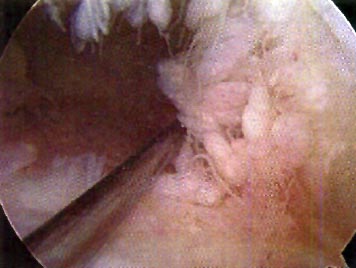

Se envió material para aislamiento, tipificación, cultivo y antibiograma. (Fig. 1-2- y 3)

Figura 1: Exploración artroscópica.

Figura 2: Debridamiento. Toma de Figura muestra. .

Figura 3: Importante reacción sinovial